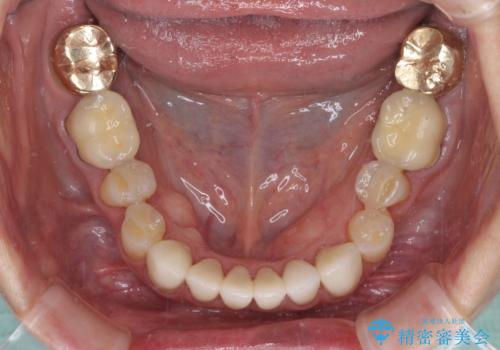

歯周外科処置を行ったことで歯周ポケットはなくなり、毎回のブラッシングの度に嫌な思いをしていた出血は認められなくなりました。

上下前歯の見え方を気にされており、歯だけをみると大変長くなりましたが、笑ったときの口元は自然な外見となり、患者様には大変満足していただきました。